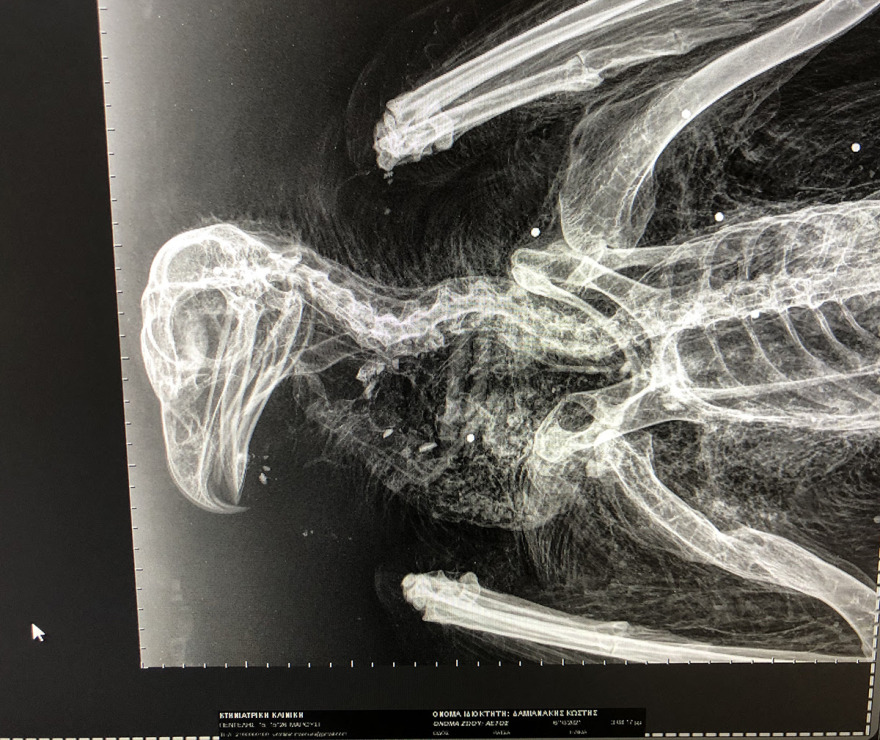

Η Ελληνική ορνιθολογική εταιρεία αναφέρει ότι τις 6 Οκτωβρίου 2021, μέλος της Ομάδας του Προγράμματος LIFE Bonelli eastMed για την προστασία του Σπιζαετού περισυνέλεξε νεκρό νεαρό Χρυσαετό μεταξύ Καπετανιανών και Λούκιας στον Δήμο Γόρτυνας. Ο προστατευόμενος αετός είχε γεννηθεί σε φωλιά στα Ανατολικά Αστερούσια Όρη πριν από περίπου ενάμιση χρόνο και είχε σημανθεί με δορυφορικό πομπό για την επιστημονική παρακολούθηση των μετακινήσεών του. Ο νεαρός Χρυσαετός υποβλήθηκε σε ακτινογραφίες και νεκροψία στην Κτηνιατρική Υπηρεσία Ηρακλείου όπου διαπιστώθηκε ότι πυροβολήθηκε στον αέρα από σχετικά κοντινή απόσταση.